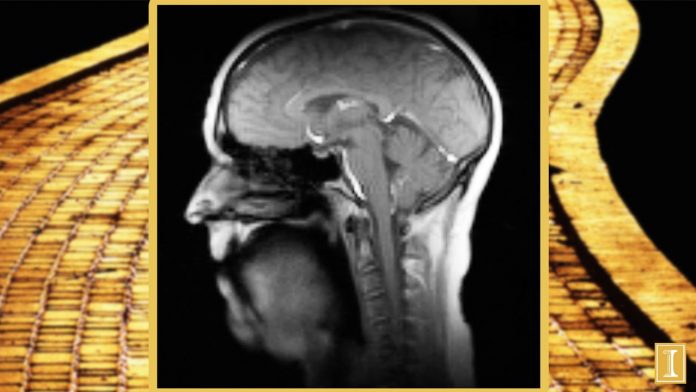

Normally, you have to stay absolutely still during an MRI, but researchers wanted to try a new technique that is 10-times faster than standard MRI scanners to illustrate how the hundreds of muscles in our neck, jaw, tongue, and lips work together to produce sound. The overall goal of the research is to see if singing in a group chorus can help people in retirement homes build stronger voices. Sounds like a worthy endeavor to me!